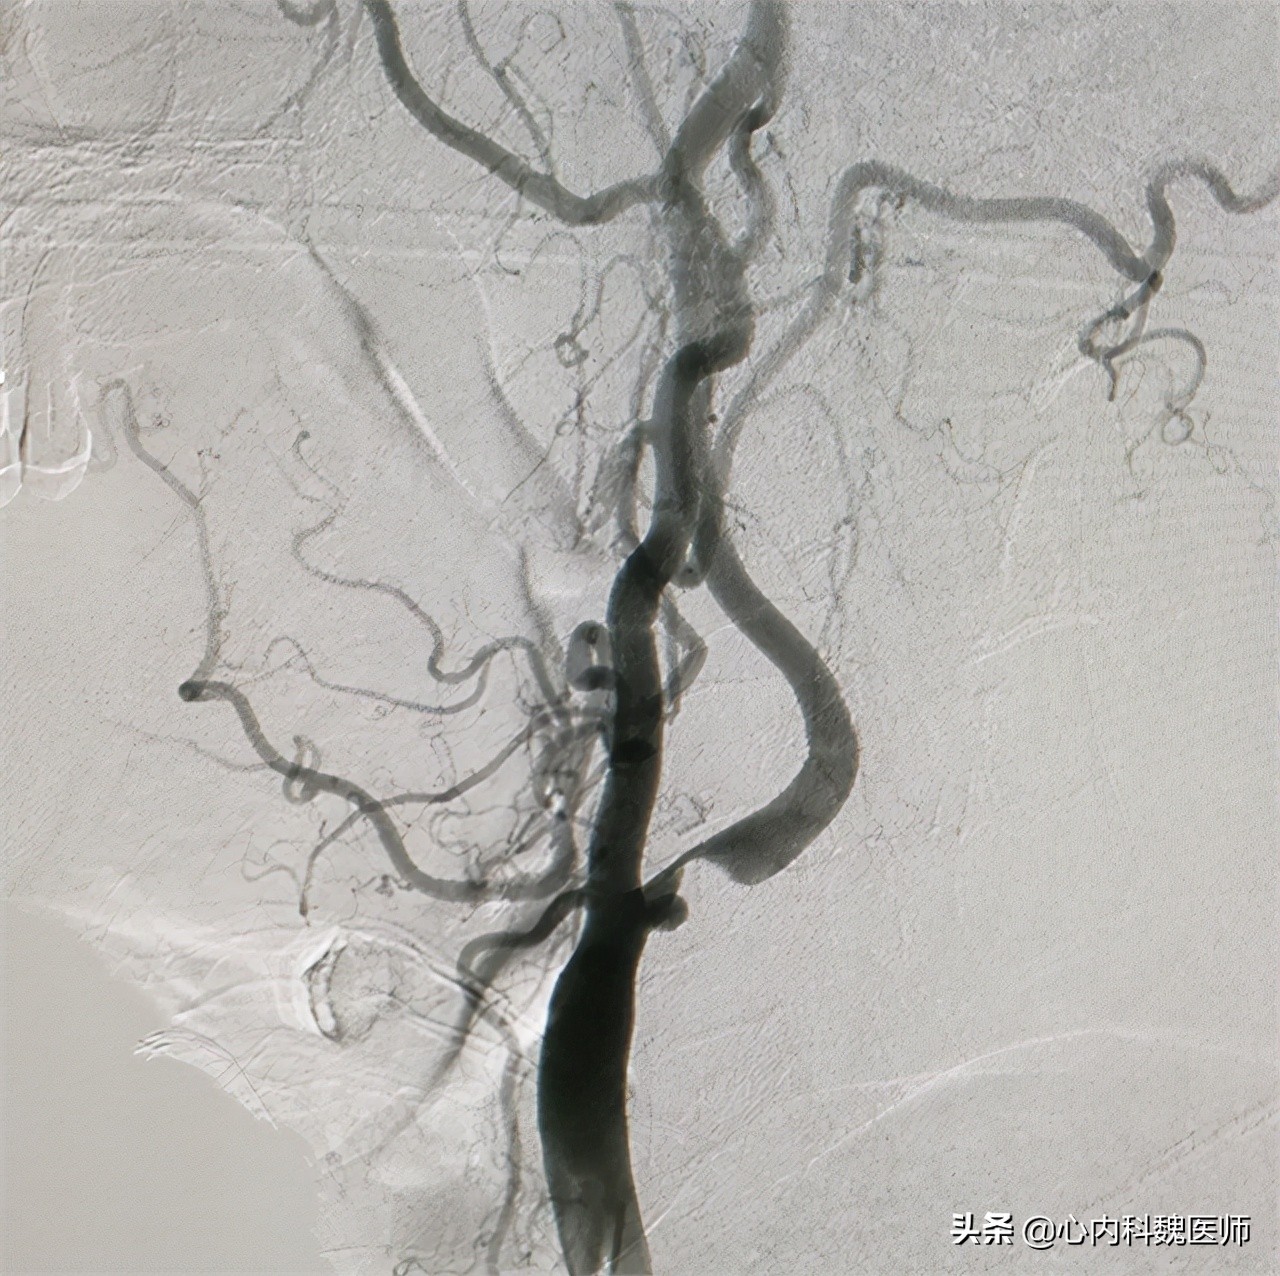

血栓缓慢地生长,脑部供血开始不足,造成头晕、嗜睡等神经系统症状,在这一阶段,医院的核磁或造影检查已经能看到明显的异常,如果及时发现,能得到有效的干预治疗。